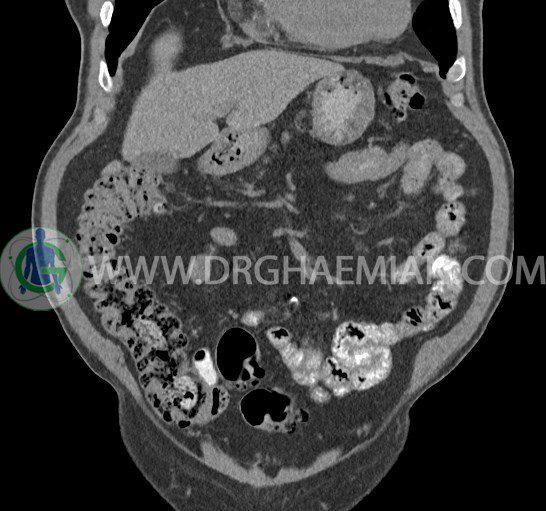

سی تی اسکن لگن یکی از روش های تصویربرداری با سی تی اسکن است. این روش با استفاده از تشعشعات تصاویر عرضی از ناحیه شکمی ایجاد میکند. در این کیس ديورتيكولوزيس، کیست های کورتیکال در هر دو کلیه، لنفادنوپاتی، کلسیفیکاسیون دیواره آئورت و شریان ایلیاک، تغییرات DJD ناحیه توراکولومبار و پروستات بزرگتر از عادی دیده می شود.

– کلسيفيکاسيون ديواره آئورت و شريان ها ايلياک همراه با نشانه هاي ترومبوز مورال در بيفورکاسيون ائورت با امتداد به پروگزيمال هاي شريان هاي ايلياک

– ديورتيكولوزيس در کولون نزولي وسيگموئيد

– تغييرات DJD در ناحيه توراکولومبار و